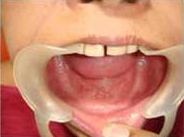

Single Tooth Implant

Placement of Abutement